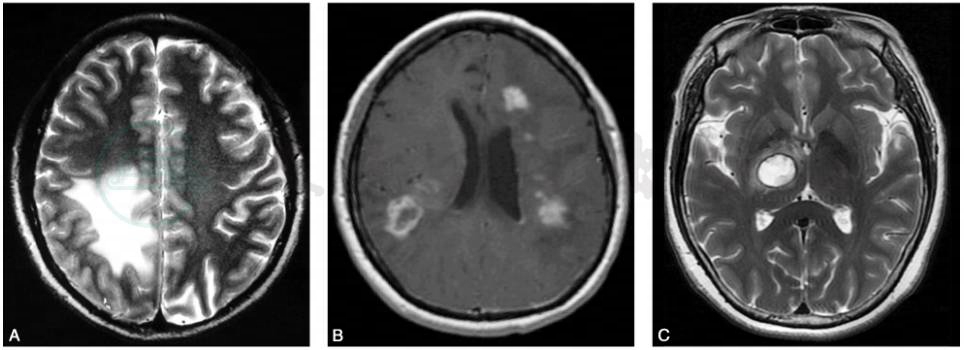

TIDD的影像学形态可见:①弥漫浸润样病灶(diffuse infiltrating lesions)较多见,病灶较大,T2WI显示病变边界较清,可呈不均匀强化,犹如弥漫浸润样生长;②环样病灶(ring-like lesions)病灶中等大小,形态为类圆形,可呈现开环形强化(多见)和闭环强化(少见);③囊样病灶(megacystic lesion)较少见,病灶较小,T1WI、T2WI均显示病灶呈高信号,边界很清楚,可呈环形强化(图3)。

图3三种不同形态学类型的TIDD

A.弥漫浸润样病灶;B.环样病灶;C.囊样病灶

引自:神经病学:全2册.第3版.ISBN:978-7-117-31406-0.主编: